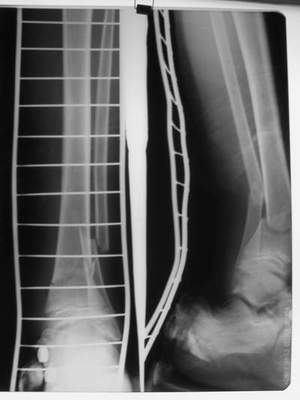

Ребенок 12 лет, поступил после падения с высоты примерно 2,5м.

Перелом костей н\3 правой голени со смещением. Перелом большеберцовой кости можно охарактеризовать как компрессионно-оскольчатый.

Скелетное вытяжение за пяточную кость.

В первые сутки значительный отек с\3, н\3голени, стопы с развитием практически неуловимого в нашей стране ;) компартмент синдрома (фасциотомии не проводилось), недочеты по укладке на скелетном

вытяжении.

Формирование некроза кожи по задней поверхности н\3 голени~ 1 %, вторичное заживление, кожная пластика. Нейропатия м\берцового нерва (отсутствие активного разгибания 1 пальца) На вытяжении около 8 нед, в дальнейшем в гипсовых повязках ~ 8 мес.

В январе 2005: варусная деформация н\3 голени, болевой с-м, комбинированная контрактура г\стопного сустава, нейропатия м\берцового нерва сохраняется слабость разгибания 1 пальца.

Операции: 1 Клиновидная резекция на вершине деформации м\берцовой кости.

2 Тугоподвижный ложный сустав н\3 б\берцовой кости. Рубцы выполняющие пространство между отломками, канал проксимального отломка иссечены.

Одномоментное устранение деформации, остеосинтез Г-образной пластиной.

Пластика по Хахутову.

Заживление проксимальной части раны вторичным натяжением без нагноения. Рана зажила. Спицы удалены через 1,5 недели после операции.